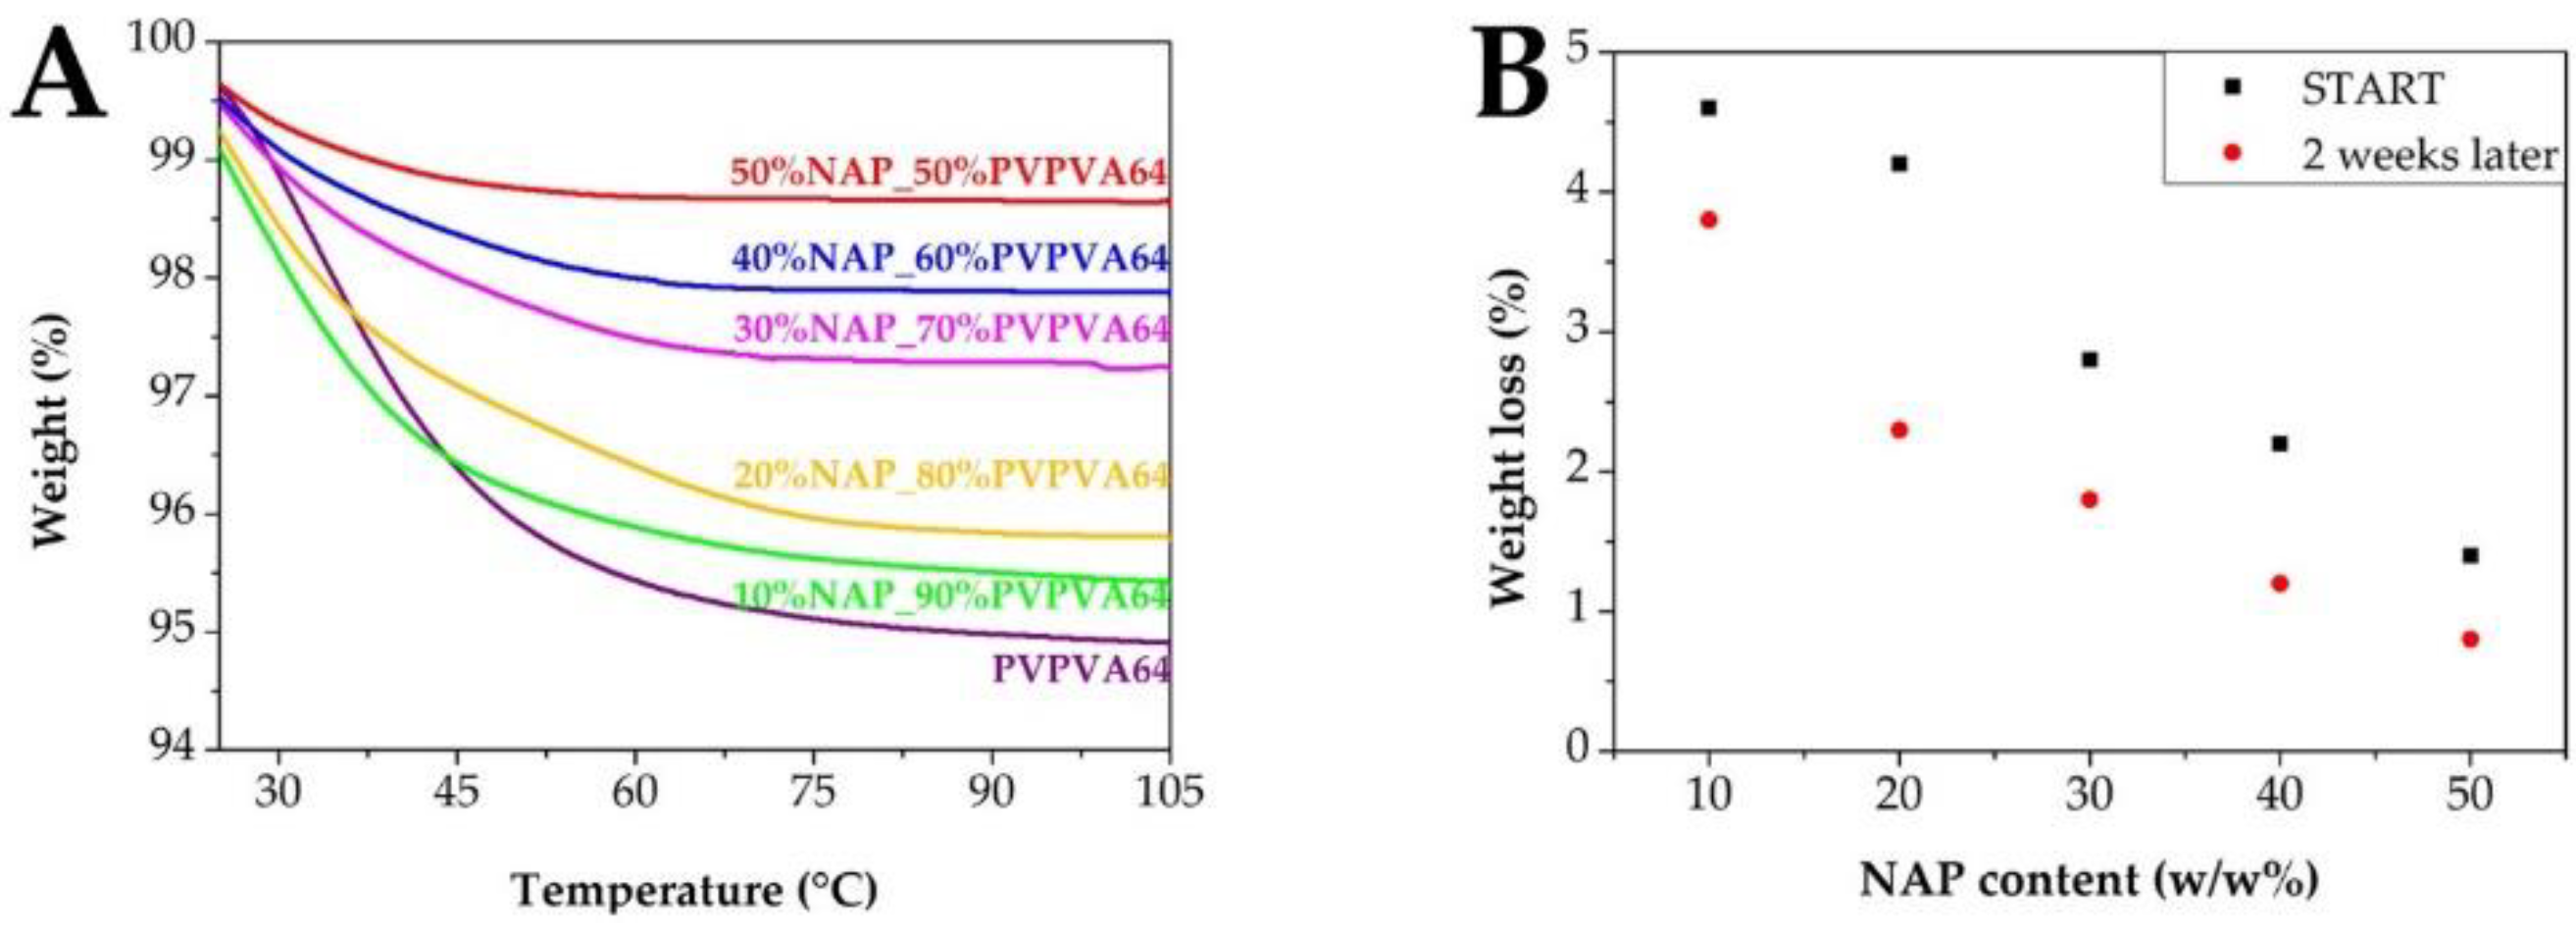

2.6. Thermogravimetric Analysis (TGA)

2.9. Stress Stability Test

3.1. Preparation and Basic Characterization of the Samples

3.3. Effect of the Stress Stability Tests